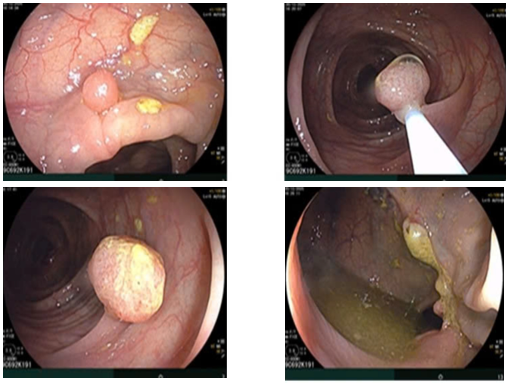

- Nội soi trực tràng:

Hình 4. Đại tràng lên, đại tràng ngang gần góc gan có 03 polyp k

ích thước~ 0,5-1cm.